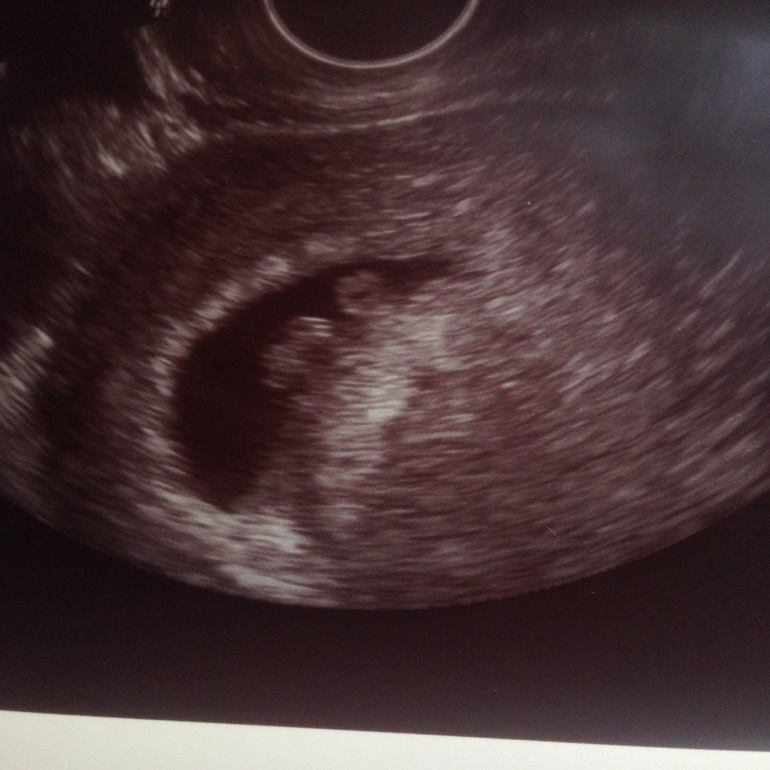

Второе узи!

Результаты: УЗИ, КТГ, доплера, скринингаДевоньки, были на втором узи, ❤️ прослушивается🙏🏼все вроде бы хорошо и соответствуют сроку, но все портит сильный тонус, сказали пить валерьянку ведрами, не сказать, что я нервничаю сильно, но видимо внутри какое то состоян е , которое я никак не могу проконтролировать😁, угрозу пока ставят(((